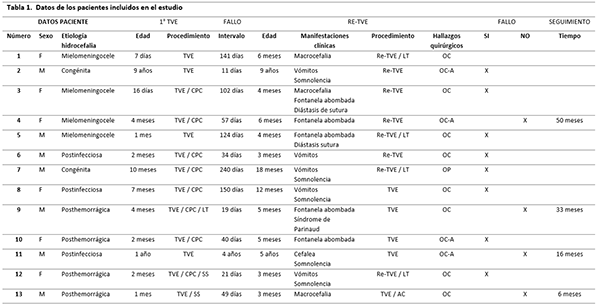

Durante el periodo de 6 años que comprendió el estudio se incluyeron 13 pacientes (7 de sexo masculino y 6 femeninos). La edad media de los pacientes fue de 18 meses, con un rango entre 3 meses y 9 años (Tabla 1).

TABLA 1: Datos de los pacientes incluidos en el estudio. AC: acueductoplastia, CPC: coagulación de plexo coroideos, F: femenino, M: masculino, LT: lámina terminalis, OC: ostomía cerrada, OC-A: ostomía cerrada con aracnoiditis, OP: ostomía permeable, SS: septostomía, TVE: tercer ventriculostomía endoscópica, Re-TVE: revisión endoscópica TVE.

Se realizaron 13 Re-TVE, 11 pacientes fueron menores de 2 años. El intervalo promedio entre la primera TVE y la revisión fue de 186 días, con un rango entre 11 días y 4 años. Con respecto al origen de la hidrocefalia, 4 (30%) fueron secundaria a mielomeningocele, 4 (30%) a hemorragia intraventricular, 3 (23%) a infecciones del SNC y 2 (15%) a patologías congénitas.

Se logró realizar la re-TVE sin dificultades a los 13 pacientes: a 12 se les realizó nuevamente la TVE y en 4 casos se llevó a cabo la perforación de la lámina terminalis. El procedimiento fue exitoso en 4 (30%) pacientes, todos menores de 2 años. En relación a la etiología y el éxito de la Re-TVE en nuestra serie, 2 fueron hidrocefalia posthemorragica, 1 postinfecciosa y 1 secundaria a mielomeningocele. En todos los pacientes en quienes no funcionó la Re-TVE, que ingresaron nuevamente con síntomas de HTE o presentaron un empeoramiento en los estudios por imágenes, se decidió la colocación de un sistema de derivación, siendo la primera opción ventrículo peritoneal.